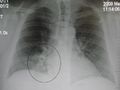

AP CXR showing left lower lobe pneumonia associated with a small left sided pleural effusion

AP CXR showing right lower lobe pneumonia

Right upper lobe pneumonia as marked by the circle.